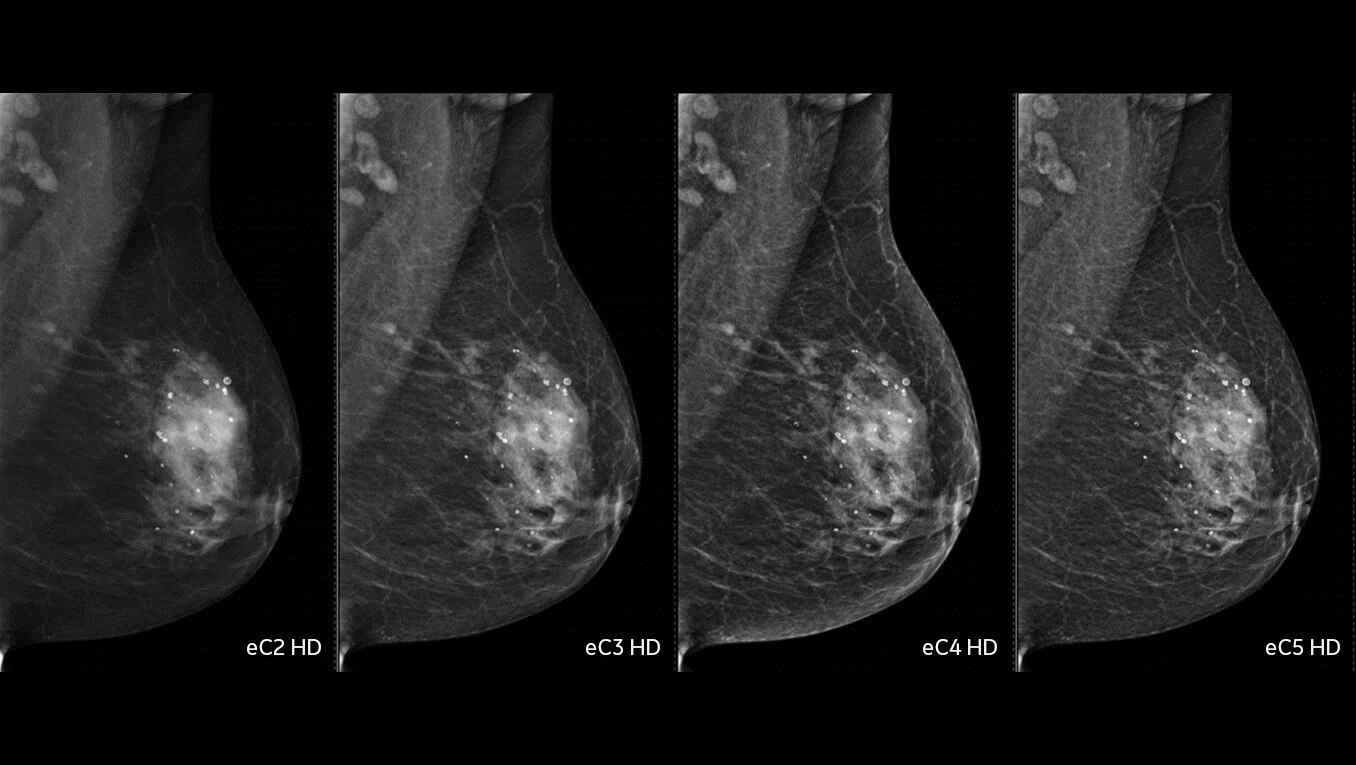

Exceptional image quality for diagnostic accuracy

Our engineering teams work passionately to develop solutions designed to achieve exceptional Image quality:

• 2D with eConstrast HD: the new processing improves the reading workflow by reducing the need to manually window our images and the radiologist confidence in our 2D image quality.

• 3D with Asir: reconstruction enables artifact management techniques that greatly reduces propagation of clips/microcalcs, at the expense of extra computation time (Asir is longer than FBP reconstruction.

• CEM with Nira: thanks to the new recombination algorithm, the impact of the artifacts is significantly reduced for all readers and may improve confidence in the diagnosis5.